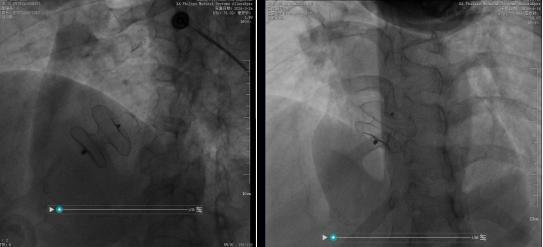

手术过程中,刘亮操作严谨,在影像设备的实时引导下,依次完成穿刺、送管、定位、释放封堵器等关键步骤。两台手术均历时数十分钟,全程患者生命体征平稳。术后即刻复查心脏彩超显示,封堵器位置固定、形态良好,房间隔缺损处无明显残余分流,手术全部达到预期效果。

图片为手术成功释放封堵器